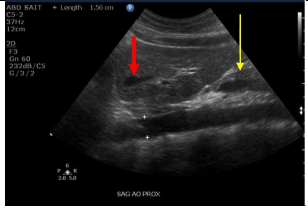

Label the red and yellow arrows

Red arrow: Left Hepatic vein

Yellow arrow: Pancreas neck